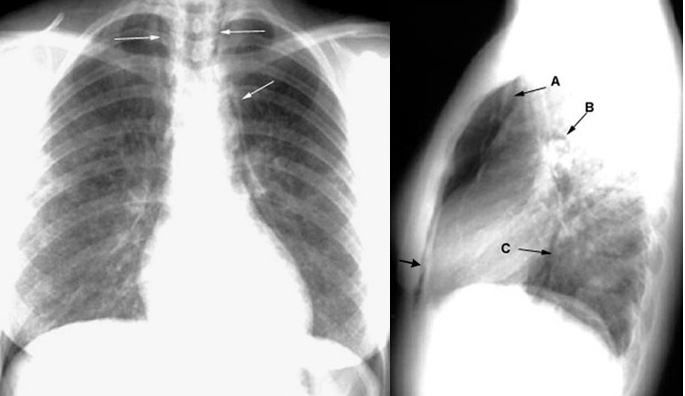

Eosinophilic Granuloma presenting with Pneumomediastinum

Reticulonodular lung fields. Arrows pointing to air along vessels. A:  Aorta/branches

B:  Pulmonary artery

C:  Descending aorta